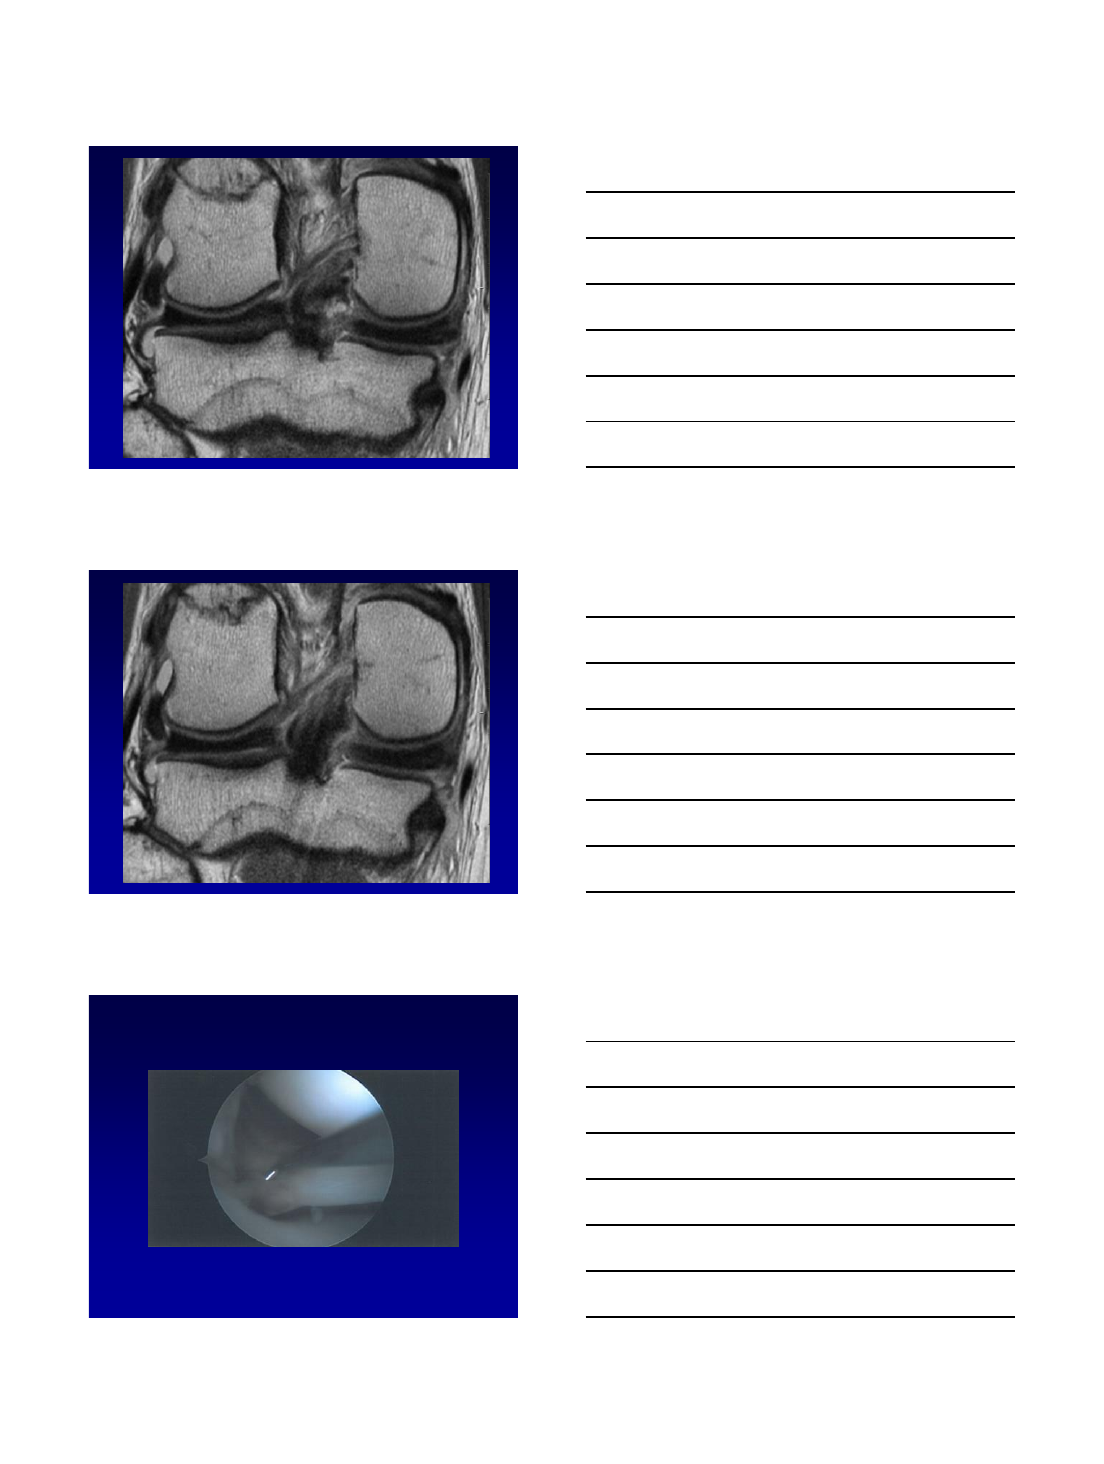

Flap tear with displacement

10/13/2015

17

•Important to recognize because gutters can be difficult to visualize

at arthroscopy

35 year-old woman with history of subtotal

lateral meniscectomy and subsequent

meniscal allograft.

•The allograft bone slot is incorporated

•Mild extrusion of the body segment

•Satisfactory position of the horns

•No meniscal split

Meniscal Allograft Transplantation